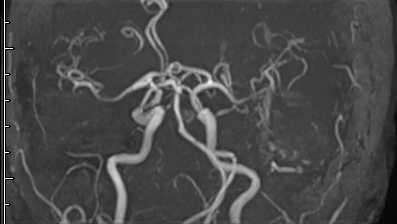

2週間程度の経過でボケてきて歩行もできなくなった。MRAにて静脈が写っています。治療後と比較してみましょう。

はい。ごちゃごちゃした部分がなくなっています。左の写真では皮膚や硬膜の血管が異常に発達して、静脈洞に盛大に逆流しています。これでは脳にまともに血液が循環しないです。高齢なので迷いましたが、治療しないわけにはいかないだろうと考え血管内治療を行いました。流入動脈を一部塞栓して勢いを落としてから、流出静脈を塞栓して、脳に逆流しないようにしました。